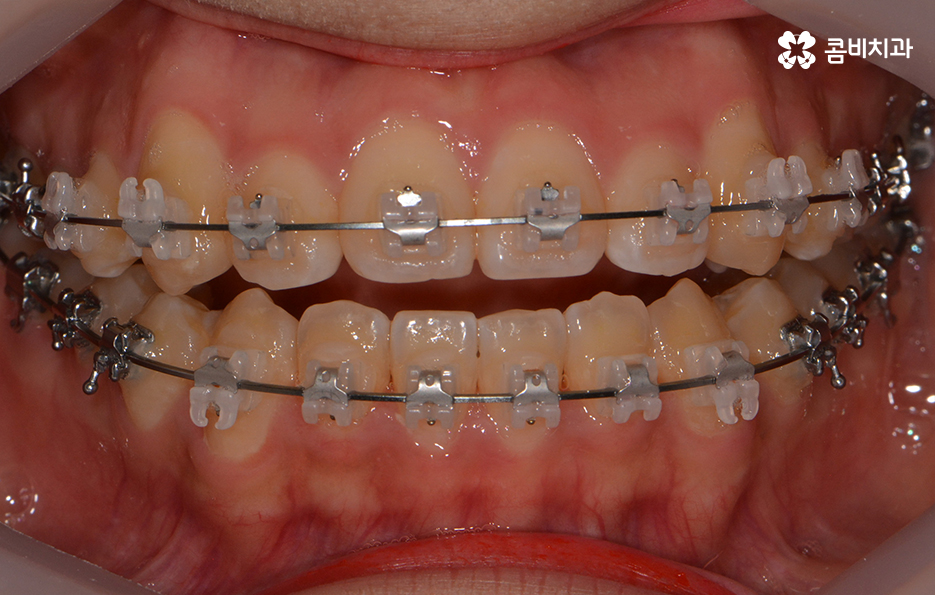

위 환자분의 경우에는 비발치로 송곳니 덧니 교정이

진행된 사례이며 전체 진료 기간은 약 1년 6개월가량이 소요되었습니다.

클리피씨 교정을 통해서 덧니가 개선되고 있는 경과

앞서 치아교정에 걸리는 기간은 어떤 교정 장치를 선택하냐에

따라서 차이가 발생된다고 말씀을 드렸는데요.

요즘 선호도가 높은 교정 장치로는 클리피씨 교정이 대표적입니다.

클리피씨 교정의 경우에는 일반적인 교정 방법에 비해서

진료 기간을 단축시킬 수 있다는 장점이 있는데

자가 결찰 장치로 서서히 치아를 지속적으로 이동시켜서

초기 통증은 줄이고 교정 기간의 단축이 가능합니다.

또한 교정 장치의 재질이 세라믹이기 때문에

심미적이라는 장점이 있으며 철사로 인한 찔림이

없다는 점에서도 편리함이 있는 장치입니다.